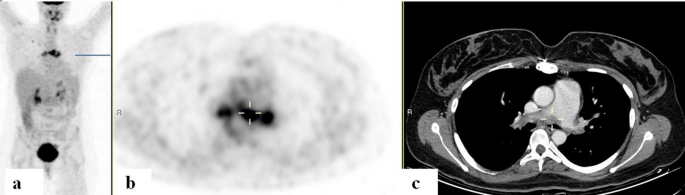

Figure 1 Of 3 patients with a history of treated GPA, PET/CT studies revealed aortitis in 2. The PET/CT scans obtained from patients with HES, RA, PsO, Behçet's, and PCNSV demonstrated evidence of vasculitis in at least 2 large vessels. The scan from a patient with IgG4 disease displayed increased uptake in the large pulmonary arteries (Fig. 2).

Figure 2 FDG-PET/CT: FDG-PET/CT:Â maximum intensity projection (MIP) (a) a representative PET (b) and CT (c) axial slices. A 31-year-old woman with IgG4-related disease with biopsy proven pulmonary arteritis. PET demonstrated increased uptake along the main pulmonary artery walls (cursers) with corresponding filler defects adjacent to the internal walls of the vessels on CT.